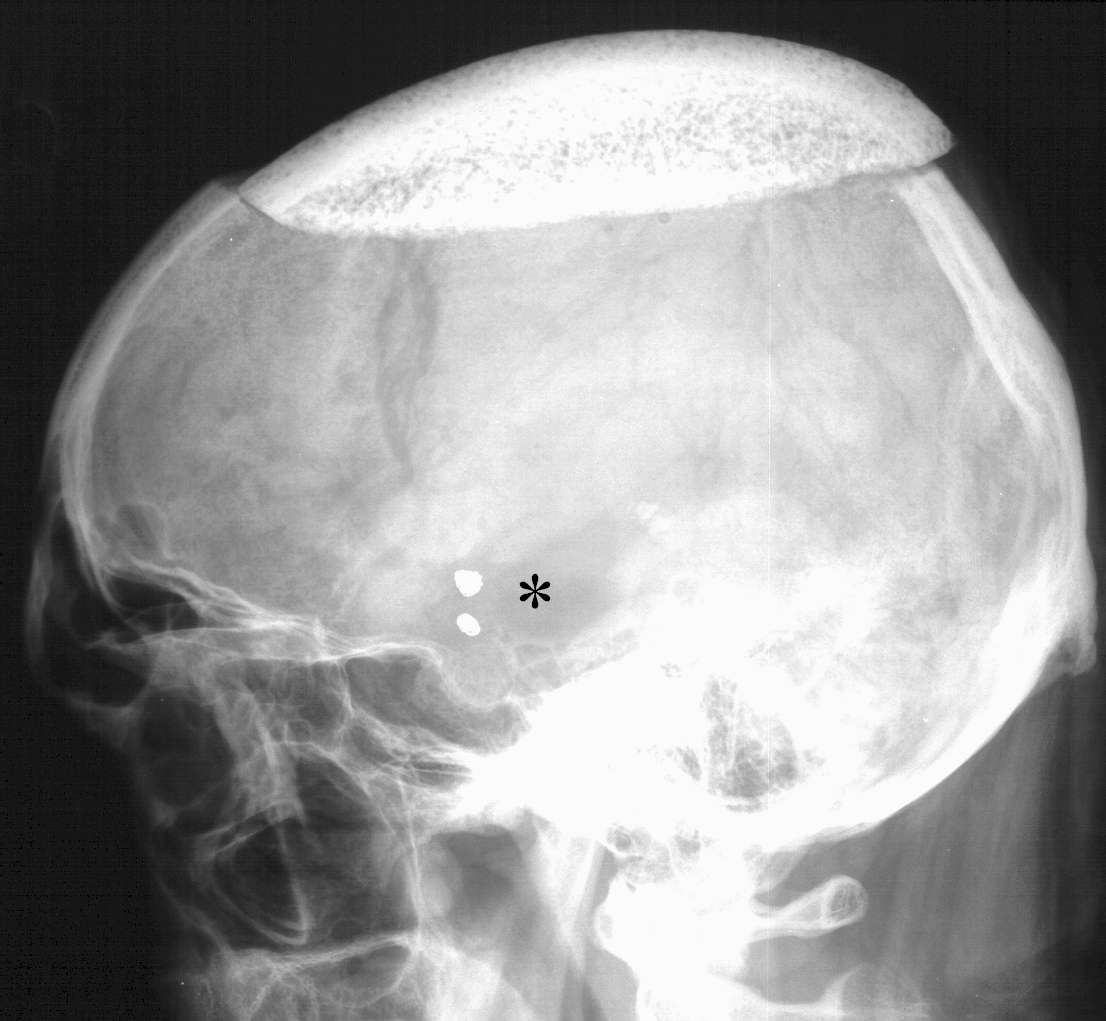

Nel caso della dislocazione (Figura 13) si può rendere necessario un nuovo intervento chirurgico per il riposizionamento.

Figura

13. Rx cranio in latero-laterale che mostra una dislocazione

posteriore della protesi in idrossiapatite. Da notare (*) che il

Paziente è stato anche embolizzato con spirali di Guglielmi di ben

due aneurismi (della dicotomia carotidea interna e della

biforcazione di destra) riscontrati, quali reperti occasionali,

durante le indagini preparatorie per la cranioplastica. |